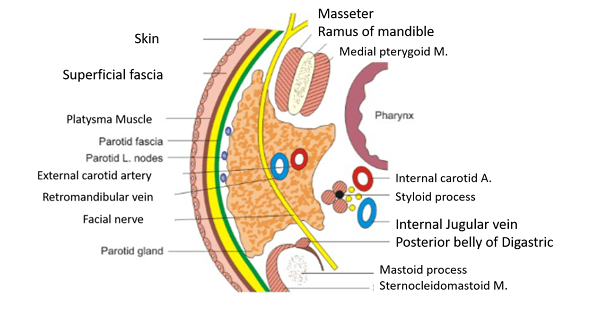

Parotid space

- Parotid g.

- Facial n.

- ECA

- Retromandibular v.